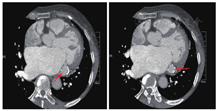

患者女性,53岁,因"反复胸闷,活动后气促"就诊,查体:呼吸20次/min,脉搏104次/min,血压121/89 mmHg。心界向左扩大,心率110次/min,心房颤动节律,心尖可闻及3/6级收缩期吹风样杂音。既往有高血压病史,规律服用贝那普利10 mg/d,血压控制不佳。心电图提示:持续性心房颤动(图1)。经胸壁超声心动图(TEE)提示:(1)二尖瓣重度关闭不全致左房、左室增大;(2)左室憩室形成(二尖瓣后瓣环)(图2)。心脏CT提示:(1)左心增大,二尖瓣后叶根部-左心室后下壁膨出瘤(真性)可能;(2)前降支(LAD)近端轻度狭窄约20%,第二对角支(D2)起始处中度狭窄约60%(图3)。为排外冠状动脉病变行冠状动脉造影检查,结果提示:右冠优势(+),左主干(LM)、LAD、回旋支(LCX)、右冠状动脉(RCA)未见明显狭窄(图4)。

可见左心增大,二尖瓣后瓣根部-左室后下壁局限性变薄并向外呈囊袋状凸出(箭头所示),大小约2.1 cm×2.0 cm,瘤颈约0.7 cm,边缘见钙化